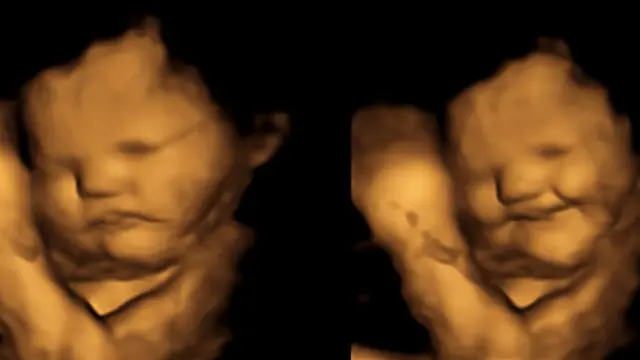

हालै मात्र वैज्ञानिकहरूले गर्भमा रहेको भ्रूण आमाले गाजर खाँदा प्रसन्न हुने र केलको साग खाँदा ठुस्स पर्ने कुरा पत्ता लगाएका छन्।

फोरडी प्रविधिबाट प्रत्यक्ष प्रतिक्रिया अवलोकन

अनुसन्धानमा संलग्न टोलीले 'साइकोलजिकल साइन्स' जर्नलमा प्रकाशित विवरणअनुसार गर्भवती महिलाले ती चक्की खाएको २० मिनेटपछि पेटमा हुर्किँदै गरेका बच्चाहरूले प्रतिक्रिया व्यक्त गरेका थिए।

फोरडी अल्ट्रासाउन्ड स्क्यानिङमा केलको चक्की खाएका आमाको पेटमा रहेका बच्चाले मुख बिगारेका थिए भने गाजरको चक्की खाएका आमाका बच्चाहरू मुस्कुराएका थिए।

डरम यूनिभर्सिटीका अनुसार यो अध्ययनबाट गर्भमा रहेका बच्चाहरूले विभिन्न स्वादमा प्रत्यक्ष प्रतिक्रिया व्यक्त गरेको कुरा पहिलो पटक पत्ता लागेको हो।